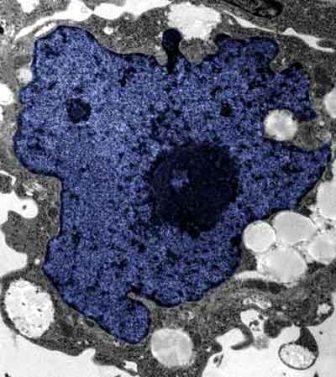

在成人體內(nèi)及胚胎內(nèi)發(fā)現(xiàn)的干細胞屬于主細胞,能發(fā)育成各種各樣的組織,可作為人體“修補工具箱”,取代死去及腐壞細胞組織。此前,最可行的干細胞為胚胎干細胞,但它的使用一直受到爭議,因為要在胚胎抽取干細胞會令胚胎死亡,有人認為這樣是變相奪走一條生命。

2007年,日本京都大學(xué)教授山中伸彌為首的科研小組證明,利用病毒倒撥普通皮膚細胞的“生理時鐘”,可把它們變成像胚胎干細胞那樣具備“變身”能力的細胞。但利用病毒把基因輸入細胞,有可能導(dǎo)致癌癥。這即是說使用這些細胞的風(fēng)險很大。

來自英國和加拿大的兩組研究員所用的新方法不必使用病毒。這項新突破暗示科學(xué)家現(xiàn)在能更認真地看待在醫(yī)學(xué)中利用皮膚干細胞(即誘導(dǎo)多功能干細胞,俗稱“iPs”細胞)的前景。

這些細胞只要配以適當?shù)幕瘜W(xué)品和蛋白質(zhì),就能轉(zhuǎn)化成腦神經(jīng)元、制造胰島素的胰腺細胞、骨或軟骨、心臟肌肉,或其它多種組織。這些細胞利用病人皮膚來培育,更暗示它們不會被人體排斥。